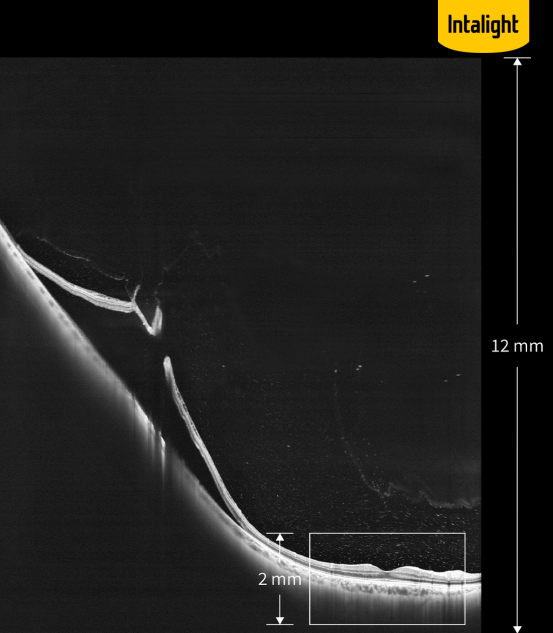

·超深度成像:全新的如意全眼OCT成像眼后节OCT最大可达12 mm超级深度成像(组织中),眼前节OCT最大可达16.2 mm成像深度(空气中),与上一代传统技术相比提升了6倍,对于以往无法完整检查的高度近视、视网膜脱离等病变也能提供完整的病变信息。

意全眼OCT眼后节12 mm超级深度成像